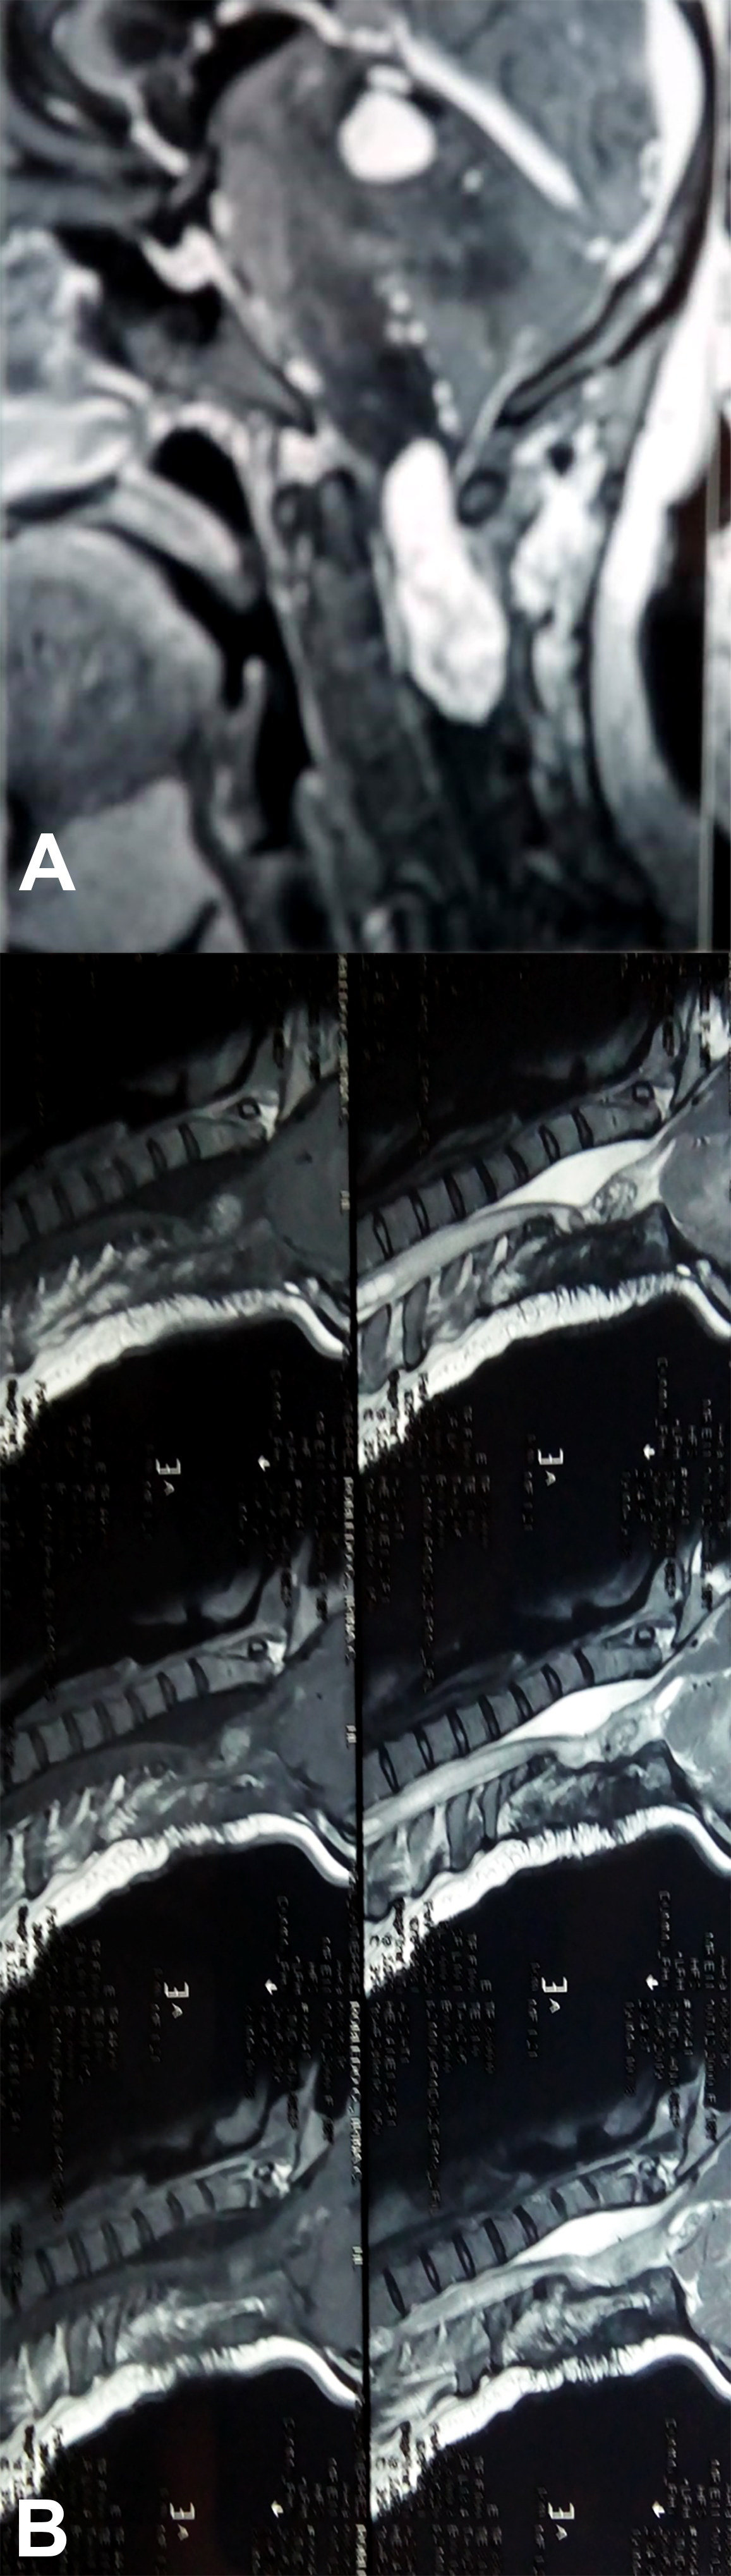

Es evidente que el límite entre el tejido medular y tumoral en las lesiones como los astrocitomas es indiscernible lo que dificulta la posibilidad de resección completa; en los tumores como los ependimomas esta diferencia es más franca y permite seguir un plano de disección seguro (Figuras 3, 4 y 5). Lo anterior condiciona nuestros resultados como han puntualizado diversos autores.5,8 El estado general previo a la cirugía requiere de una valoración juiciosa de las posibilidades de resección. Por ejemplo, el caso 12 (Figura 6) es una paciente portadora de Enfermedad de Von Hippel Lindau, Hemangioblastoma cervical biopsiado en otra institución del exterior del país, fijación de columna cervical y sindrome de Cushing por exceso de medicación corticoidea cuya cirugía debió suspenderse en dos oportunidades por la disminución de su capacidad ventilatoria. Con estos antecedentes y la delgada capa de tejido medular evidenciada intraoperatoriamente se optó por una resección subtotal. A los cuatro meses de la cirugía la paciente recuperó la marcha autónoma y demás parámetros clínicos.

Figura 3: Caso 10. Ependimoma cervical pre operatoria: Lesión sólida C3 y dilatación siringomiélica. Posoperatorio: resección completa, disminución de la cavidad. Restos hemáticos decantados.

Respecto del monitoreo intraoperatorio, la utilidad del registro de potenciales evocados, Onda D o Electromiografía dependerá no solo de la obtención de respuestas sino también del diálogo entre el cirujano y el neurofisiólogo,11-13 debido al fenómeno de falso negativo y positivo como se muestra en la Tabla 4. El cirujano recibe la información con retraso al evento y en ocasiones las maniobras de “reanimación” medular (irrigación con suero tibio, corticoides, etc.) no son concluyentes produciendo el abandono de una resección factible. La laminoplastía busca favorecer la restitución del alineamiento espinal, pero debe mantenerse un control, en particular en tumores de la unión cérvico dorsal, sobre el desarrollo o acentuación de escoliosis (Figura 3), en ocasiones presente al diagnóstico y que se acentúa en la evolución posoperatoria.13,16

El caso del Neurocitoma cérvico dorsal (Figura 4), debido a su excepcionalidad, requiere un análisis particular lo cual realizaremos en una comunicación separada.